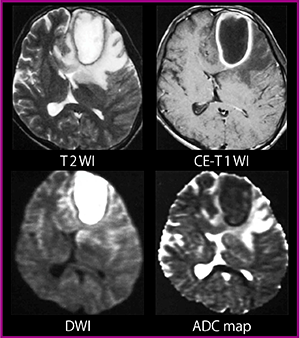

拡散強調画像は,特に急性期脳梗塞の診断に用いられるが,膿瘍や類上皮腫においても有用な情報を提供する。図2の脳膿瘍症例(20歳代,男性)は,拡散強調画像で高信号を示している。ADC mapでのADC値低下を確認し,膿瘍であると診断できる。

類上皮腫は,T1強調画像やT2強調画像では脳脊髄と同等の信号を示すが,拡散強調画像では高信号となることから診断に有用である。

図2 脳膿瘍(20歳代,男性)